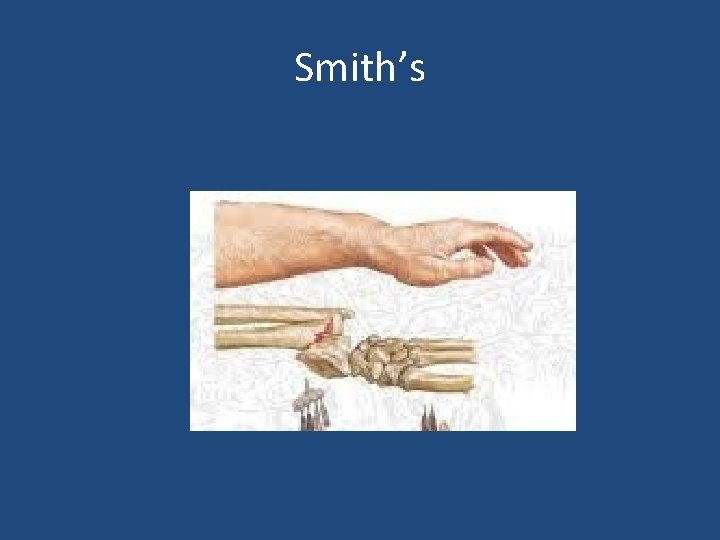

• Extra-articular: – Colles’ Fracture: dorsal angulation, shortening and radial deviation – Smith’s fracture: shortening and volar angulation. (reverse Colles’) • Intra-articular: – Barton’s fracture: volar or dorsal – others

Smith’s